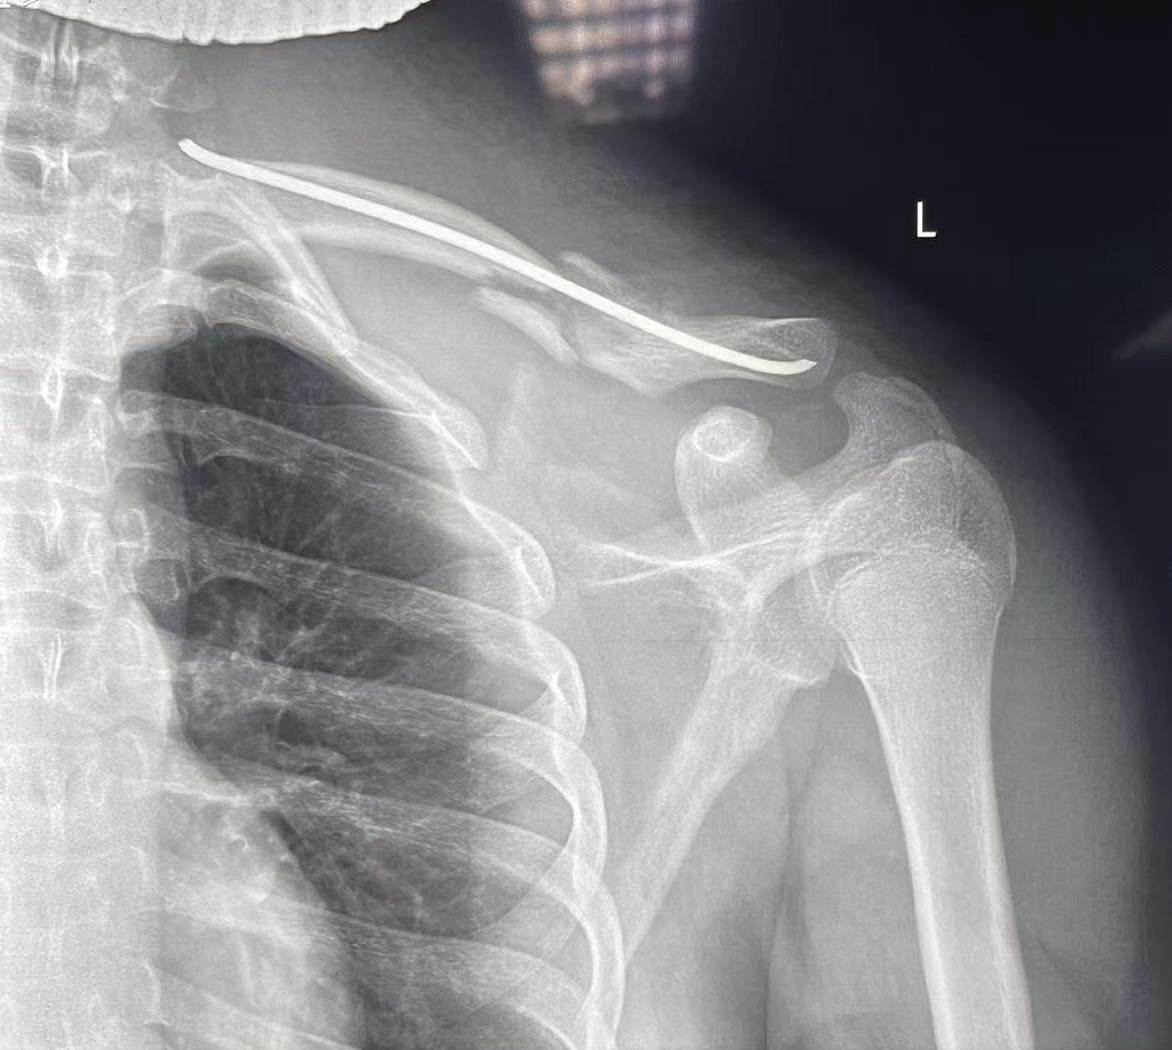

术后影像

考虑到小高已是初三年级,为了能够尽快恢复,尽量不影响小高的学习、生活,主诊医师赵朝锋为小高采用闭合穿针技术治疗,效果良好。赵朝锋表示:“闭合穿针技术是一种微创手术,创伤小、恢复快,对小高来说是最合适的,术后不用佩戴较多辅助器具,对日常活动的影响较小,而且这种微创手术的创口很小,不会对小高将来的学业和职业发展造成太大影响。”